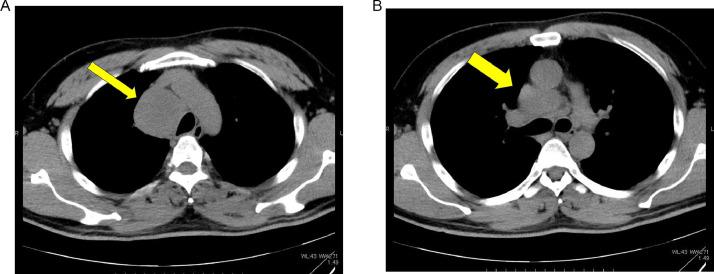

Thoracic -deficient undifferentiated tumor (-UT) is characterized by an undifferentiated rhabdoid morphology and deficiency pathologically. In the 2021 revision of the WHO classification, it was categorized as an epithelial tumor because of its shared genetic background with smoking-related lung cancer. We describe the case of a 44-year-old man with a rapidly enlarging mediastinal mass observed on chest radiography and CT. The tumor was resistant to radiation therapy, chemotherapy, and immune checkpoint inhibitors, and the patient's survival time was approximately 5 months. Familiarity with the clinical background and imaging findings of thoracic -UT is crucial for early diagnosis and treatment planning.

胸段发育不全未分化肿瘤(-UT)的特征是具有未分化的横纹肌样形态且病理表现为发育不全。在世界卫生组织(WHO)2021年的分类修订版中,因其与吸烟相关肺癌具有共同的遗传背景,它被归类为上皮性肿瘤。我们描述了一名44岁男性的病例,胸部X线和CT检查发现其纵隔肿块迅速增大。该肿瘤对放射治疗、化疗和免疫检查点抑制剂均耐药,患者生存时间约为5个月。熟悉胸段-UT的临床背景和影像学表现对于早期诊断和治疗规划至关重要。